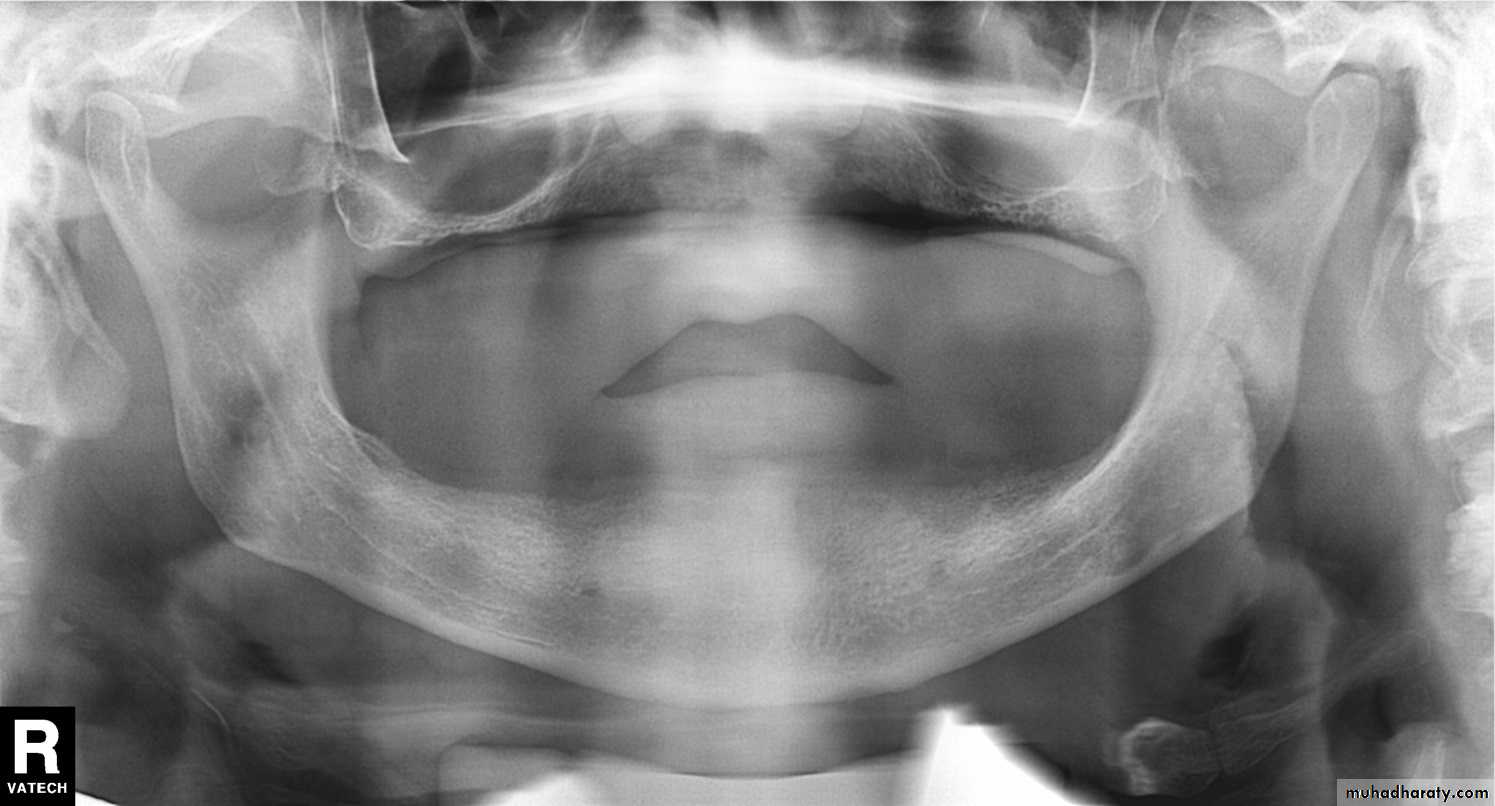

In a good panoramic radiograph:

The mandible is “U” shaped.

The condyles are positioned about equal distance from the inside edges of the image and 1⁄3 of the way down from the top edge of the image.

The occlusal plane exhibits a slight curve or “smile line,” upwards.

The roots of the maxillary and mandibular anterior teeth are readily visible with minimal distortion.

Magnification is equal on both sides of the midline.